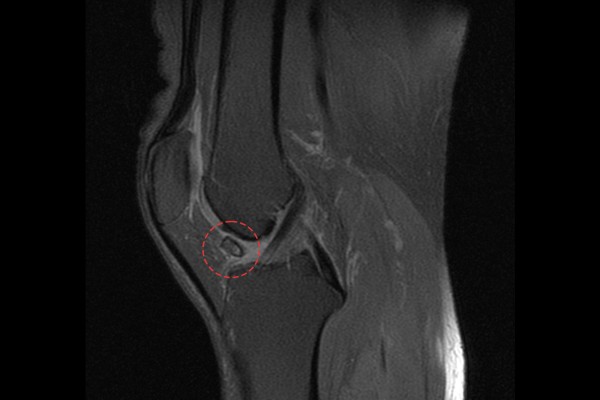

MRI 검사를 했을 때 역시 무릎 관절 내에 유리체(뼛조각)가 확인되어 무릎 관절 내 유리체(뼛조각)(Bony loose body knee Rt.)을 진단하였습니다.

통증이 지속되었기 때문에 수술적 치료인 관절경하 관절 내 유리체(뼛조각) 제거술(Rt. knee A/S (loose body removal))을 진행하기로 하였습니다.

수술 후 MRI를 확인해봤을 때 무릎 관절 내 유리체가 잘 제거된 것이 확인됩니다.